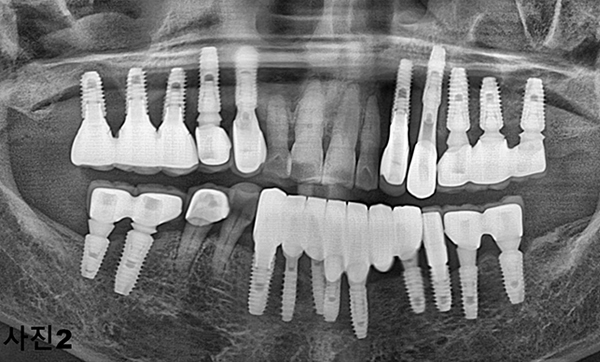

틀니를 상담하기 위해 내원한 50대의 환자로써 (사진1 ) 파노라마사진을 촬영하고 구강검진(사진2) 하여보니,

아직 나이도 젊고 일반 틀니로서는 기능회복이 어려울 것 같아 임플란트를 이용한 똑딱이 틀니를 설명하였다.

그러나 환자가 틀니 대신에 고정성 보철물을 문의하기에 환자의 구강상태, 전신 건강상태, 치료비의 감당능력을

서로 상의하고 상하악에 최소 4개씩 식립하고 풀아치 고정성 보철물을 제작하기로 하였다.